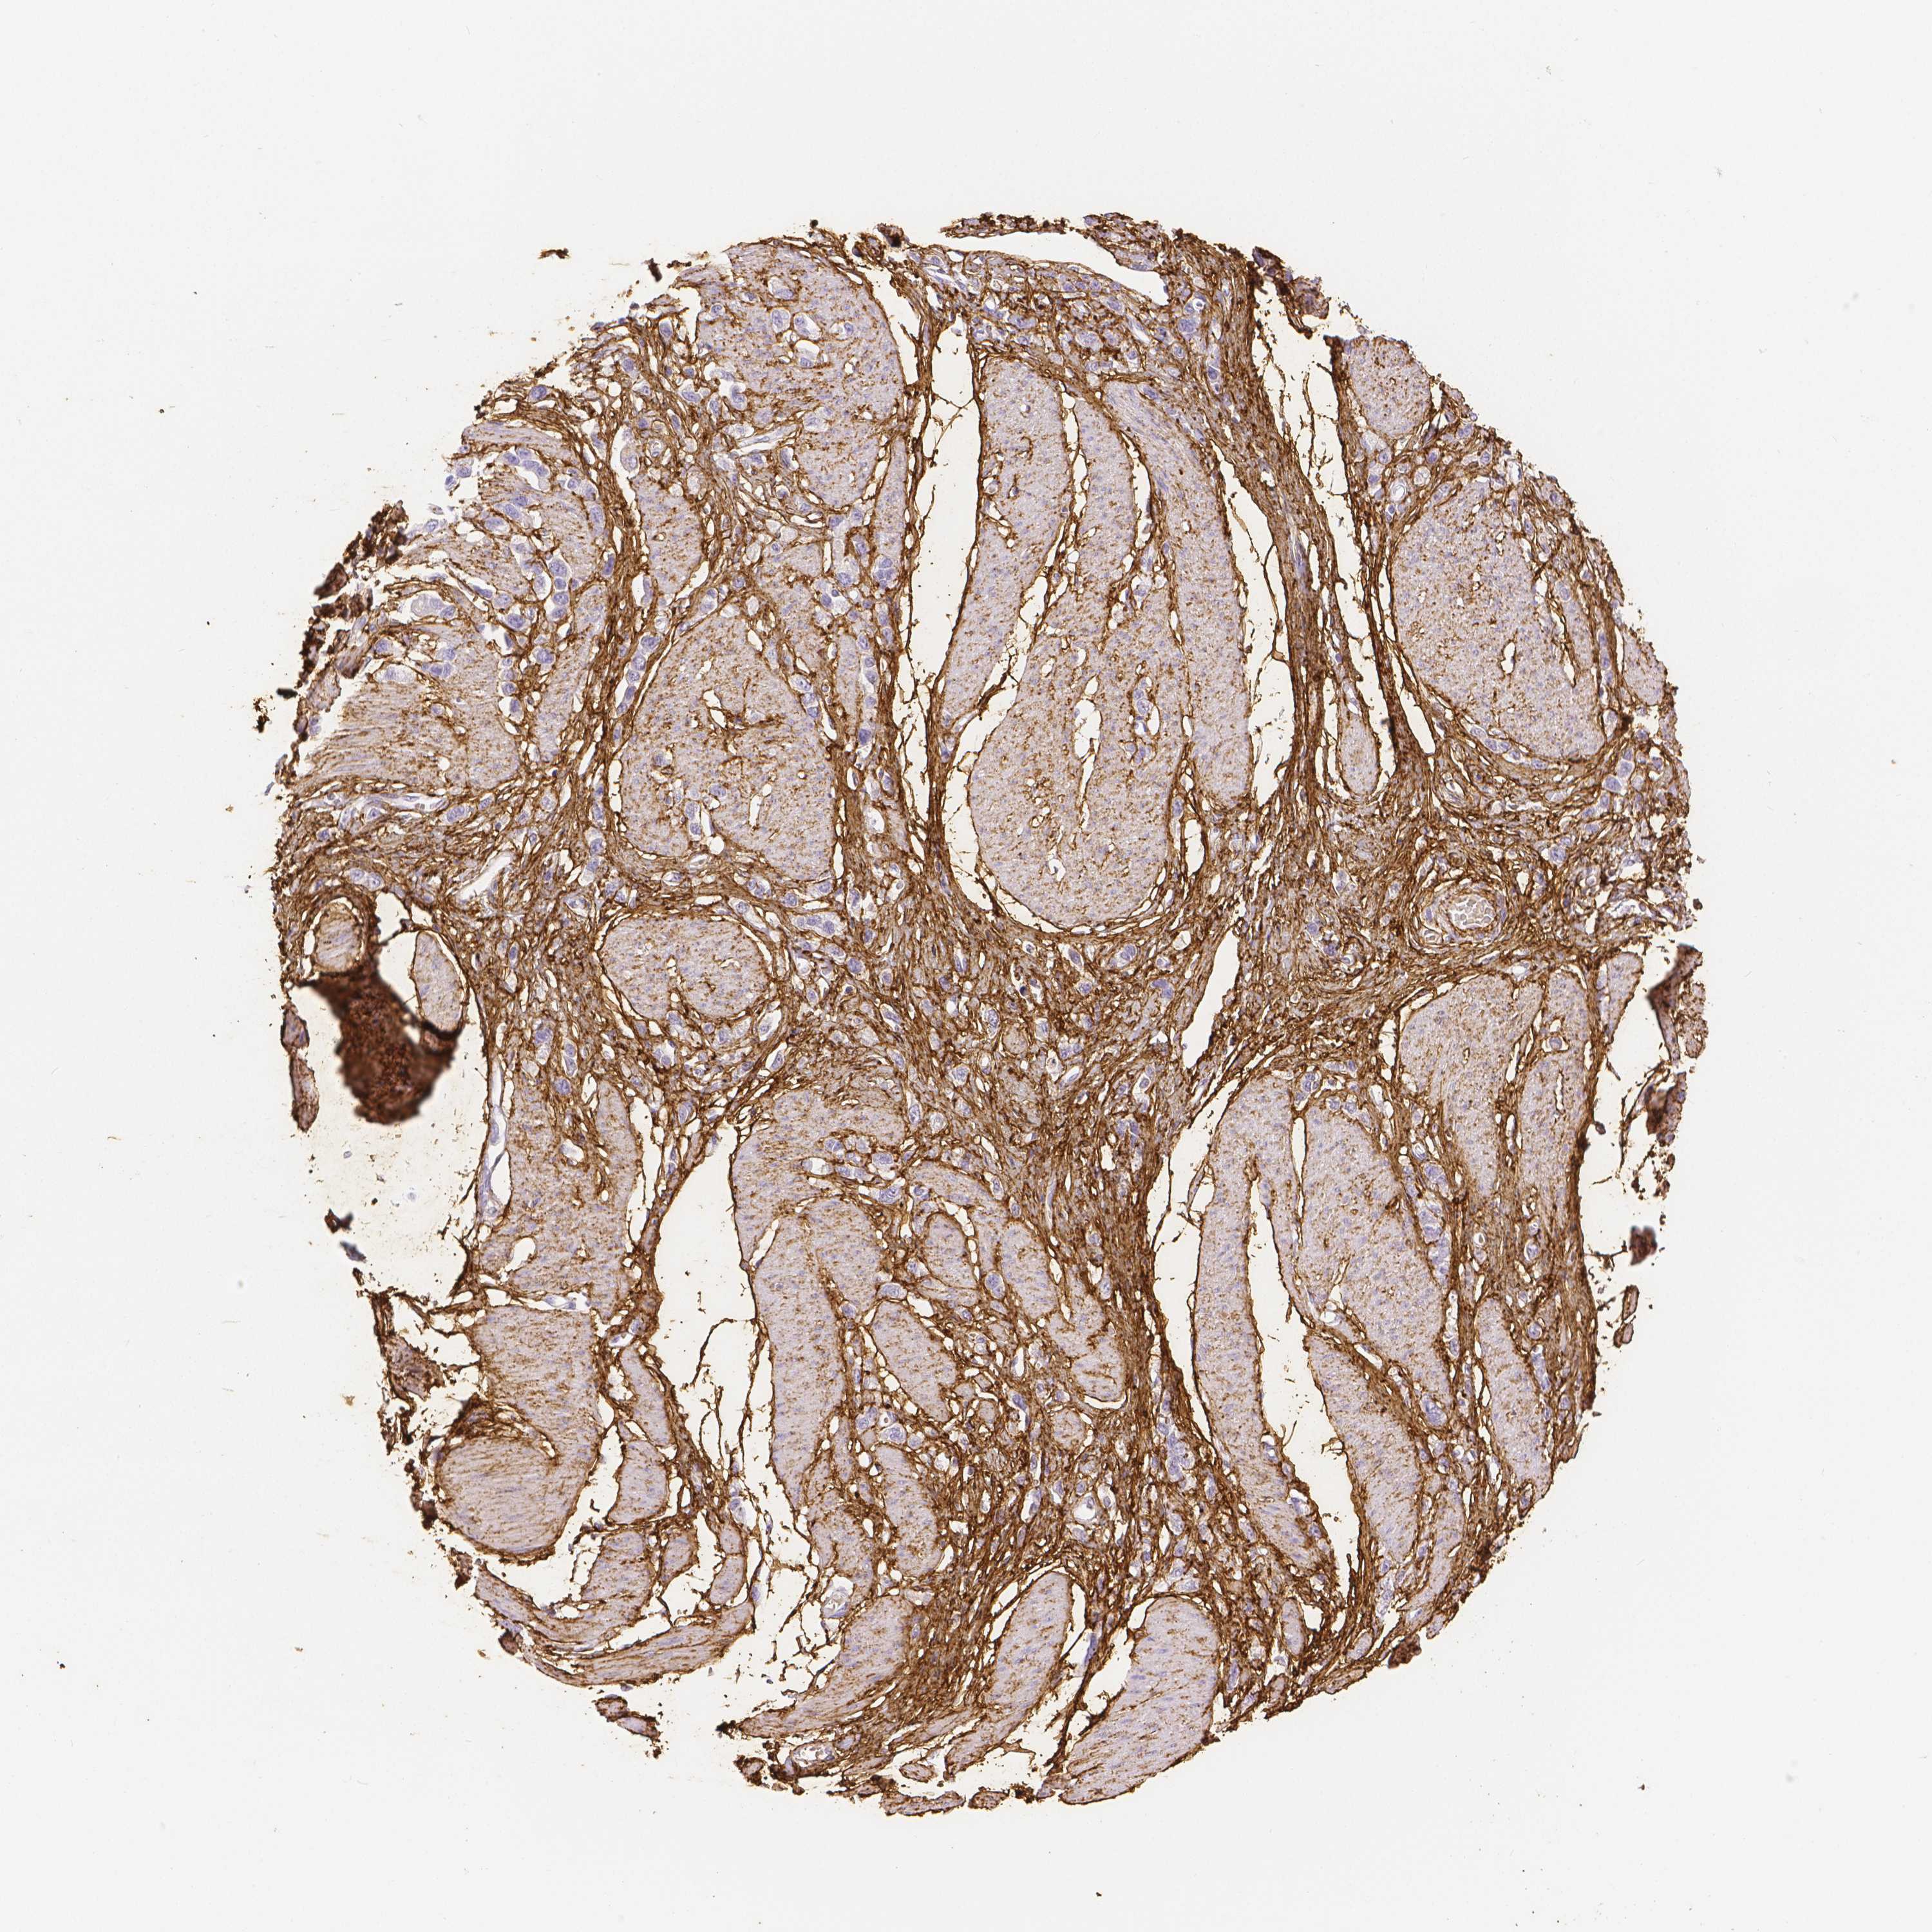

STOMACH CANCER - Protein expressioni

A mouse-over function shows sample information and annotation data. Click on an image to view it in a full screen mode. Samples can be filtered based on level of antibody staining by selecting one or several of the following categories: high, medium, low and not detected. The assay and annotation is described here.

Note that samples used for immunohistochemistry by the Human Protein Atlas do not correspond to samples in the TCGA dataset.

Antibody stainingi

Antibody staining in the annotated cell types in the current human tissue is reported as not detected, low, medium, or high, based on conventional immunohistochemistry profiling in selected tissues. This score is based on the combination of the staining intensity and fraction of stained cells.

Each image is clickable and will lead to virtual microscopy that enables deeper exploration of all samples and also displays staining intensity scores, fraction scores and subcellular localization as well as patient and tissue information for each sample.

HPA017759

HPA021057

CAB002670

CAB058696

CAB068188

CAB080202

Staining

High

Medium

Low

Not detected

Intensity

Strong

Moderate

Weak

Negative

Quantity

>75%

75%-25%

<25%

None

Location

Nuclear

Cytoplasmic/membranous

Cytoplasmic/membranous,nuclear

Adenocarcinoma, NOS

Adenocarcinoma, High grade